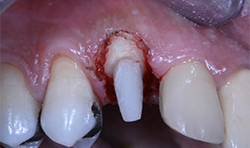

A 46-year-old male patient presents with pain on tooth #6. He stated he was traveling overseas in four days for an extended period of time and would like treatment to be completed.

A digital periapical X-ray (PA) (Fig. 12) was taken using Air Techniques ScanX phosphor plates. The PA revealed caries into the pulp. The tooth would require endodontic therapy, a post core and a crown.

Root canal therapy was completed (Fig. 13).

A carbon fiber post and composite core buildup was completed (Fig. 14), and a soft tissue crown lengthening was performed with a diode laser at a setting of 2W continuous pulse mode.

Fig. 14

Fig. 15

Fig. 14 Fig. 15

A digital scan (Fig. 15) was taken using the Planmeca Emerald. The total scan time of the preparation, the upper arch and the lower arch was less than two minutes.